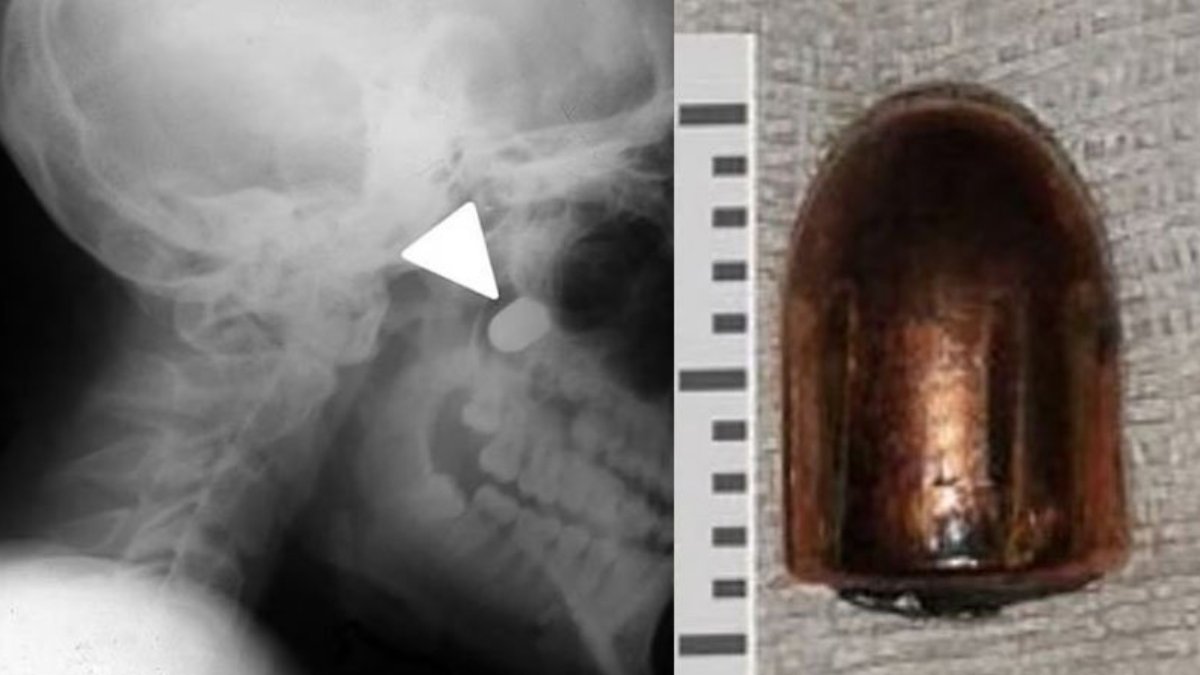

Adı açıklanmayan 16 yaşındaki sivil kurban, Sovyet yapımı bir tabancayla ensesinden vuruldu. Doktorlar, kurşun yarasına bakarak, çocuğun Makarov tabancasıyla yaklaşık 15 cm'den vurulduğunu tahmin ettiklerini belirttiler.

9 mm'lik merminin boyna girdiğini, omurganın ucunu sıyırdığını ve üst çeneye saplandığını gördü. Genç, Ukrayna'nın merkezindeki Vinnytsia şehrinde bir hastaneye götürüldü. Çocuğun yüzünün sol tarafı ve boynu şiş; omuriliğindeki hasar nedeniyle ağzı tam olarak açılamıyor ve sol kolunu da kaldıramıyordu.

Ameliyat sırasında doktorlar çenesinin alt kısmından bir kesi yaparak bölgedeki yumuşak dokuyu parçalara ayırdı ve mermi kabuğunu kafatasından çıkardı.

Daha sonra bölgeyi tedavi edip yarayı diktiler. Çocuk, ameliyattan dokuz gün sonra hastaneden taburcu edildi. Ve şaşırtıcı bir şekilde tamamen iyileşti.